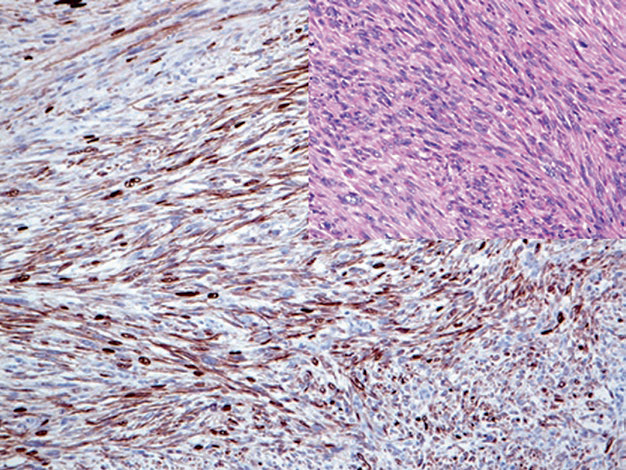

图3. 胚胎性横纹肌肉瘤中,EGFR强阳性表达。